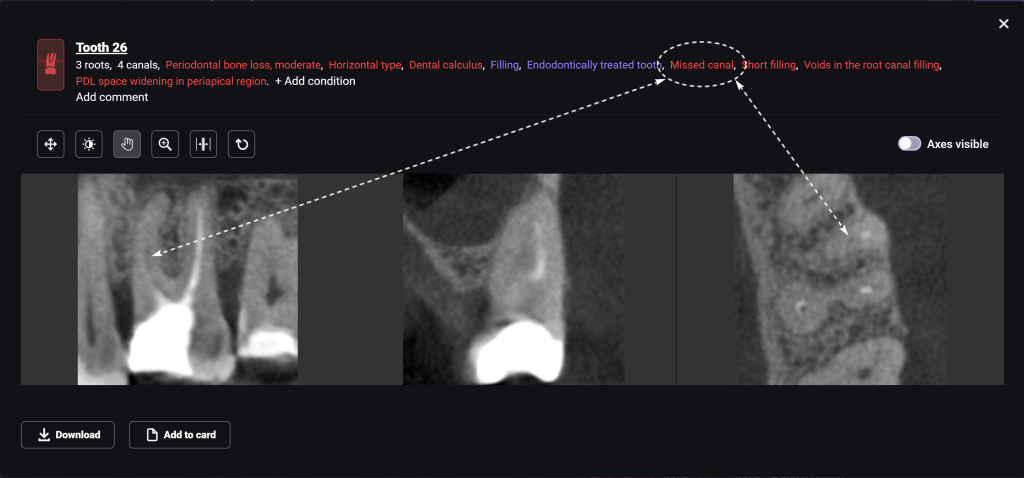

Diagnocat AI helps us to see not only the consequences, but also the causes of the pathology. For example, in this clinical case – the missed MB2 during previous endodontic treatment of tooth 26 (Universal 14)

The 3D-Viewer allows the clinician to align the axes according to the area of interest and to study root canal morphology and anatomy before starting a treatment